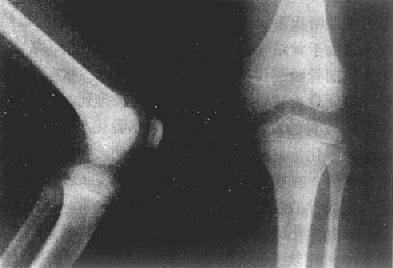

图2-1-2 儿童正常膝关节

X线上,由于软骨、关节囊都是软组织密度,不能显示,所以,相对骨端之骨性关节面间呈半透明间隙,称之为关节间隙(joint space)。因此,X线所见关节间隙包括了关节软骨及其间的真正微小间隙和少量滑液。两个相对骨端的骨性关节面光滑整齐,相距匀称,间隙清晰,宽度均匀(图2-1-4)。关节间隙的宽度因部位和年龄而异。

图2-1-4 正常成人膝关节

股骨下端和胫骨上端的骨性关节整齐,间隙清晰,宽度均匀